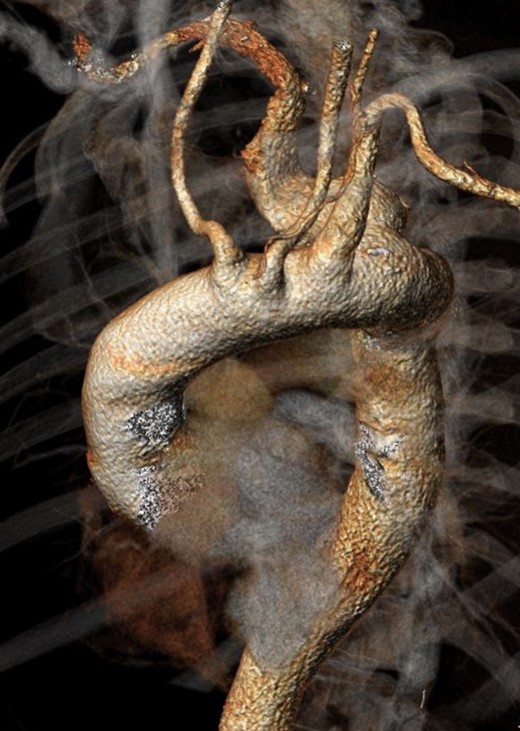

Twenty-two months after the procedure, the patient referred to our Unit due to the worsening of dysphagia. A new CT scan showed the enlargement of the aneurysmal sac (115 mm) due to the persistent Type II endoleak from bronchial arteries (Fig. 3). An endovascular embolization of the target vessels was not feasible due to the impossibility to cannulate the bronchial arteries without direct puncture. A preoperative esophageal endoscopy was performed to exclude the presence of esophageal–aneurysmal fistulas and an open repair with right thoracotomy and aneurysmorraphy of the AARSA was performed to occlude the bronchial side branches and to reduce the compression of the giant aneurysm on the esophagus (Fig. 4, 5). The postoperative course was uneventful and the patient was discharged on the 11th postoperative day.

Angio-CT scan at 22 months showing Type II endoleak with significant sac enlargement.